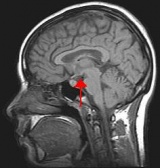

内耳前庭器是人体平衡感受器官,它包括三对半规管和前庭的椭圆囊球囊半规管内有壶腹嵴,椭圆囊球囊内有耳石器(又称囊斑),它们都是前庭末梢感受器,可感受各种特定运动状态的刺激。半规管感受角加(减)速度运动刺激,而椭圆囊、球囊的囊斑感受水平或垂直的直线加(减)速度的变化。当我们乘坐的交通工具发生旋转或转弯时(如汽车转弯,飞机作圆周运动),角加速度

晕动病

作用于两侧内耳相应的半规管,当一侧半规管壶腹毛细胞受刺激弯曲形变产生正电位同时,对侧毛细胞则弯曲形变产生相反的电位(负电),这些神经末梢兴奋或抑制性电信号通过神经传向前庭中枢并感知此运动状态;同样当乘坐工具发生直线加(减)速度变化,如汽车启动、加减速刹车、船舶晃动、颠簸,电梯和飞机升降时,这些刺激使前庭椭圆囊和球囊的囊斑毛细胞产生形变放电,向中枢传递并感知。这些前庭电信号的产生、传递在一定限度和时间内人们不会产生不良反应,但每个人对这些刺激的强度和时间的耐受性有一个限度,这个限度就是致晕阈值,如果刺激超过了这个限度就要出现运动病症状。每个人耐受性差别又很大,这除了与遗传因素有关外,还受视觉、个体体质、精神状态以及客观环境(如空气异味)等因素影响,所以在相同的客观条件下,只有部分人出现运动病症状。

与运动病有关的两个感觉系统是前庭和视觉系统,前者可进一步分为半规管角加速度感觉系统和耳石器的直线加速度感觉系统。皮肤压力感受器肌肉关节本体感受器,与耳石器起协同作用。前庭系统功能状况在运动病的发生上起重要作用。丧失前庭功能的聋哑人不易患运动病。前庭功能正常但不能适应过度强烈的刺激者会患运动病。前庭功能过敏者易患运动病。